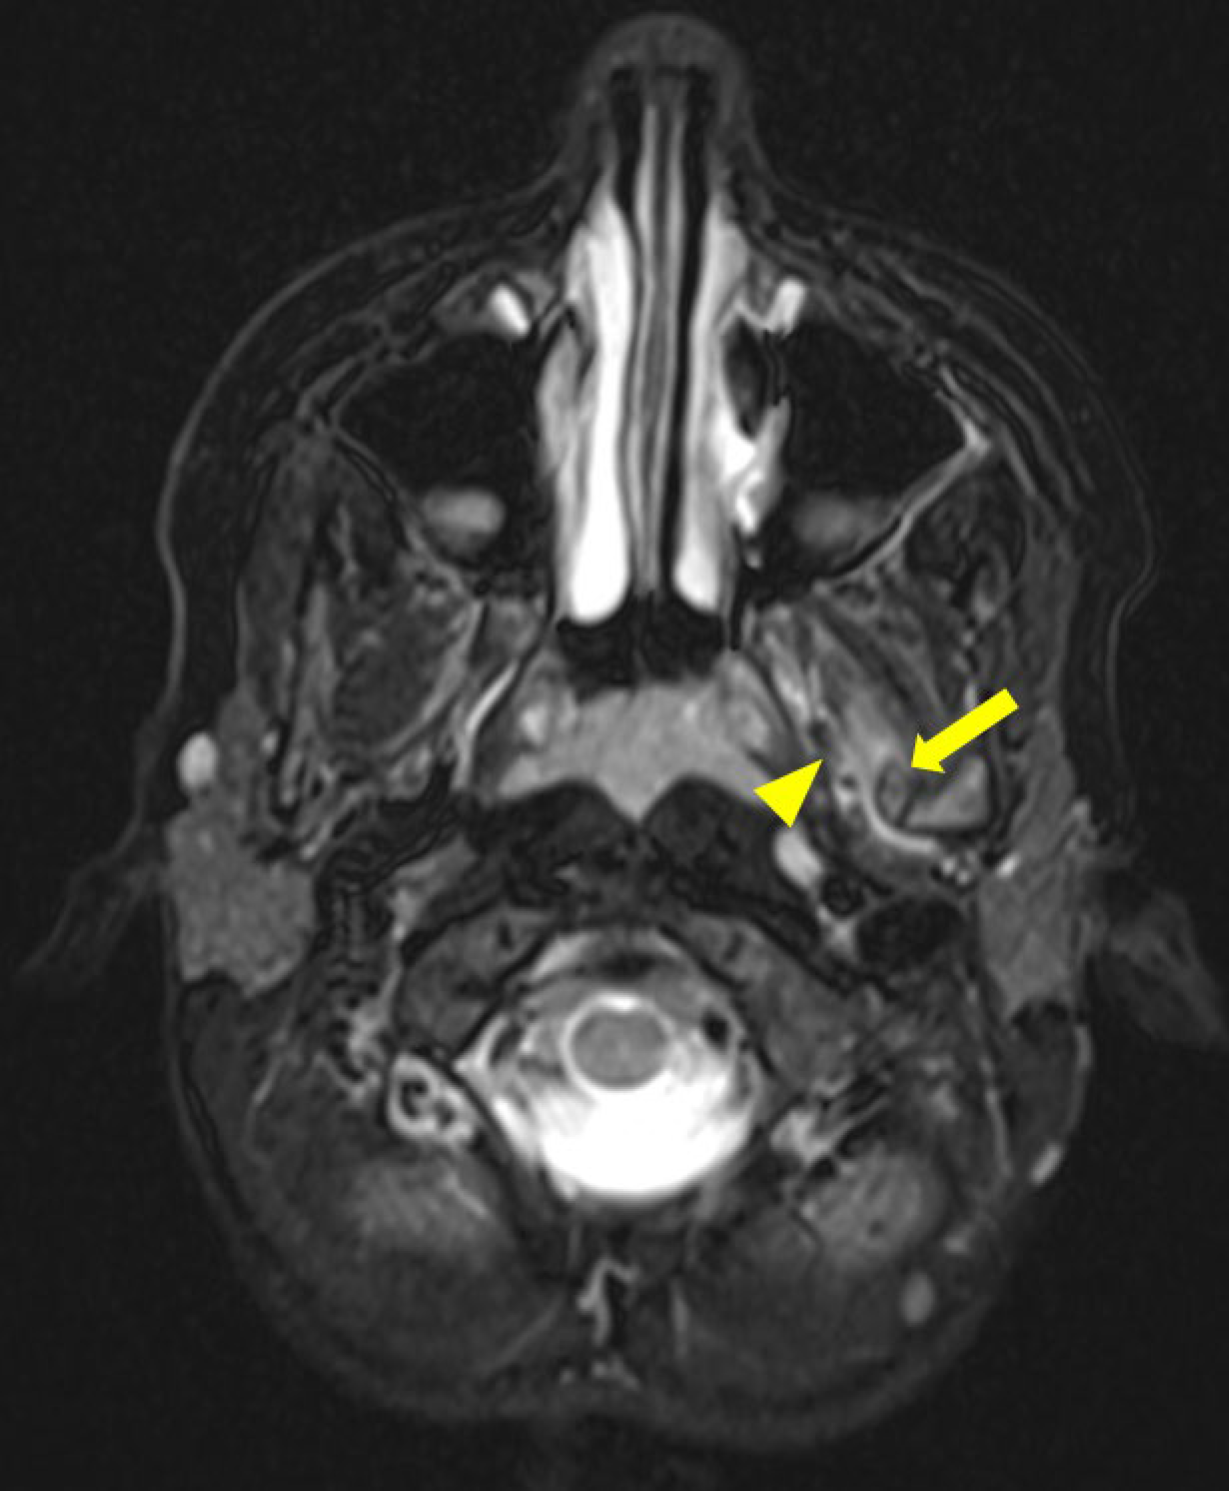

Figure 3

Axial T2 Dixon MRI scan showing edema infiltrating the lateral pterygoid muscles fibers (arrowhead) close to the ossified sphenomandibular ligament (arrow).